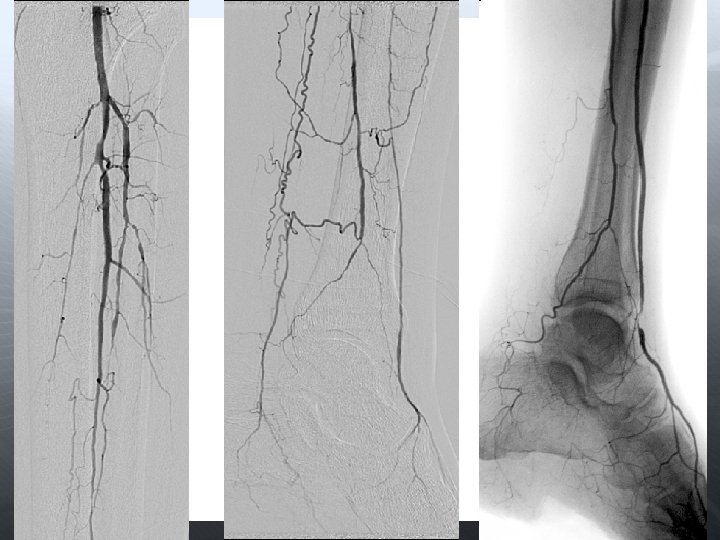

DİZALTI

Amaç uzun dönem açıklık değil, akımı restore etmek Olabildiğince çok damar restrore edilmeli Total ayak perfüzyonu iyileştirilir 3 damar run-off ile daha iyi SFA açıklığı sağlanır Oklüzyona karşı daha dirençli

Anjioplasti Subintimal anjioplasti Cutting-balon DEB Stent (BES, SES) DES Aterektomi Excimer laser